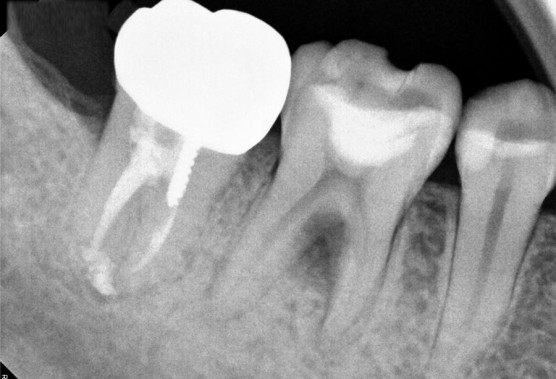

[2020.01.02 첫 내원 시 구강 상태]

아래어금니가 씹을 때 아파서 내원하셨습니다.

입안을 살펴보니 기존 수복되어있는 치아에 틈이 생겨 치수염이 생기고,

뿌리끝 부분만이 아니라 주변까지 다 염증에 이환되어있는 상태였습니다.

[치아뿌리 주변까지 염증에 이환된 상태]